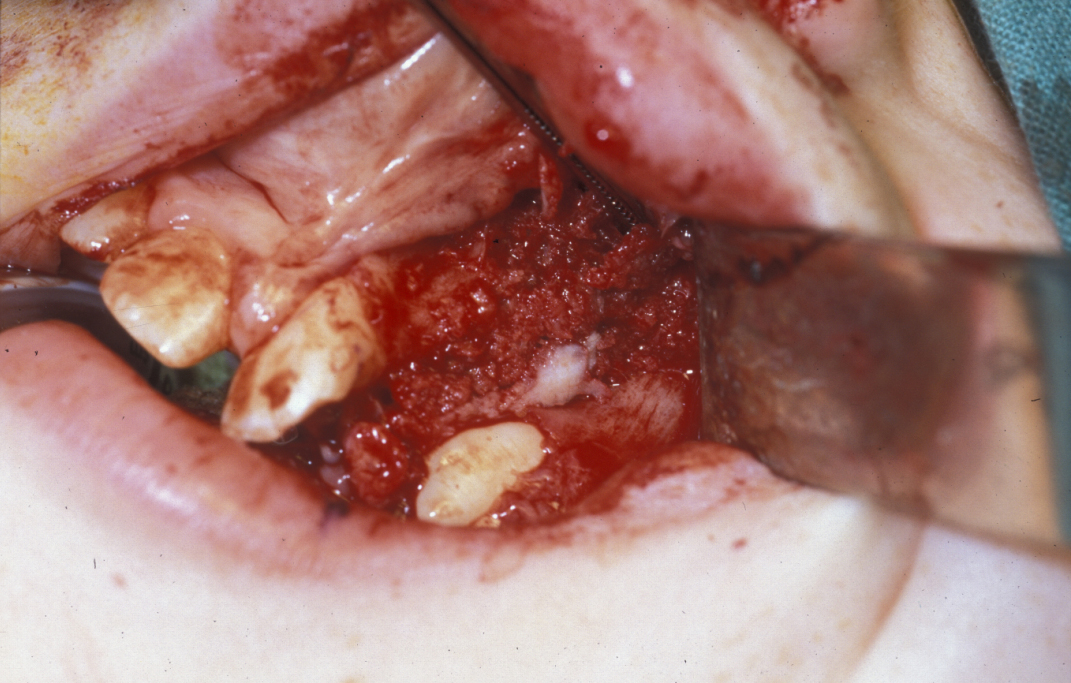

The technique of alveolar bone grafting involves outlining a buccal lesser flap and a major segment flaps. The flap in the major segment is a mini-flap. Subperiosteal dissection exposes the cleft and the lining of the oronasal fistula is incised to create two upper nasal flaps and two lower palatal flaps. These flaps are sutured to create a pyramidal shaped defect now lined by mucosa superiorly and inferiorly. This defect has either periosteum or bone on all its margins at this point, except for the base which is the labial aspect. The defect is then packed with bone which may be trephined or harvested by an open procedure from the iliac crest (hip) or the tibia (lower leg) (Figure 6).

Figure 6: The periosteum and bone-lined defect, packed with bone.